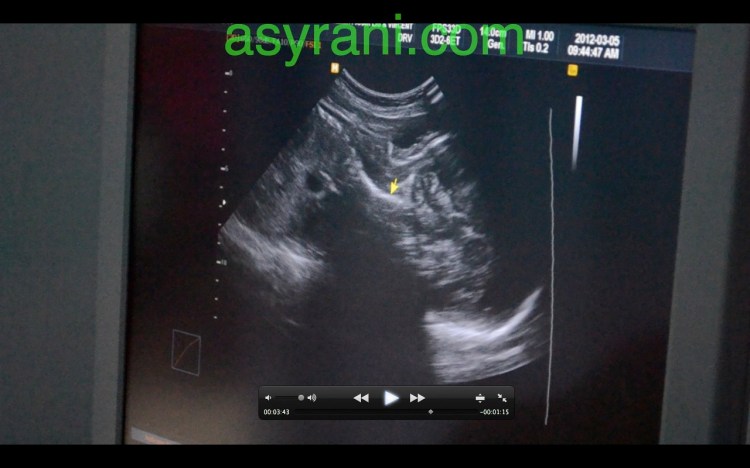

Usus dan perut baby(yang berwarna gelap tersebut)

Pundi Kencing yang dah berfungsi menurut kata Dr., jadi buah pinggang juga sudah berfungsi dengan baiknya